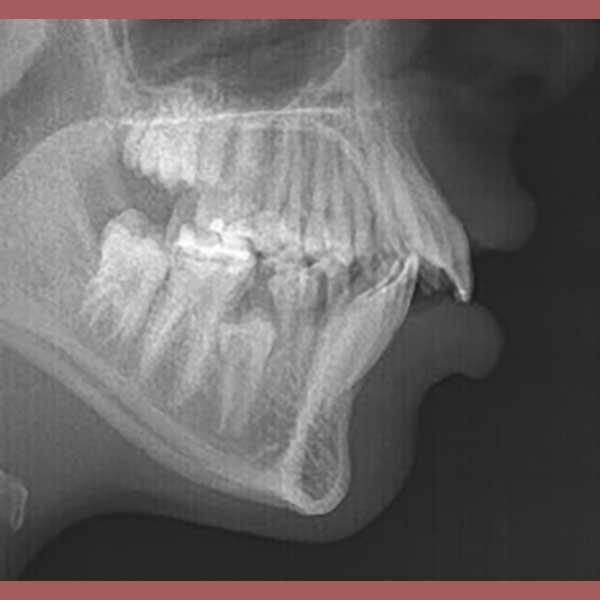

BEFORE

بعد الفحص الدقيق، وجد الدكتور خالد الكاتب أن الأسنان العلوية متقدمة على السفلية بمسافة كبيرة (8 مم)، وأن السبب الجذري للمشكلة هو تراجع الفك السفلي. ونظراً لصغر عمر المراجعة ورفض الأهل لخيار قلع الأسنان، تم وضع خطة علاج ذكية تعتمد على تقديم الفك السفلي للأمام باستخدام جهاز وظيفي ثابت، وهو خيار مثالي في مرحلة النمو.